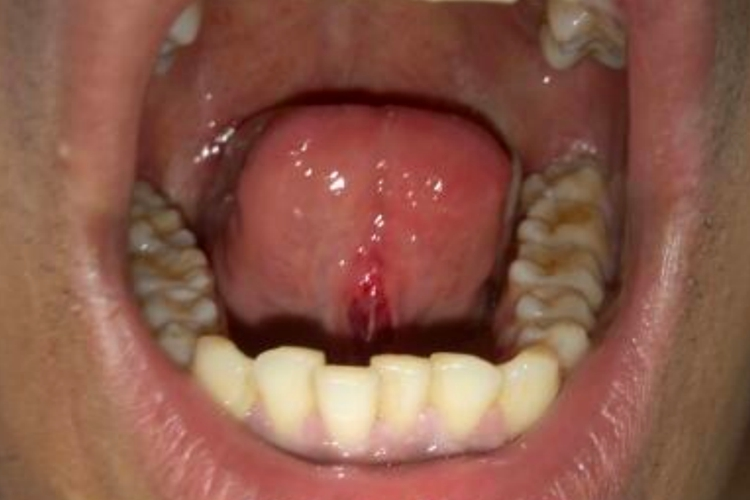

口腔尖锐湿疣

初发损害为小而柔软的粉红色丘疹,针帽或米粒大,逐渐增大至长锥形疣状物。可出现在口腔任何部位,包括舌系带处,可单发或数量逐渐增多。疣体逐渐增大,呈菜花状或乳头瘤样。表面可角化发白或有糜烂、溃疡,一般无自觉症状,可有异物感。